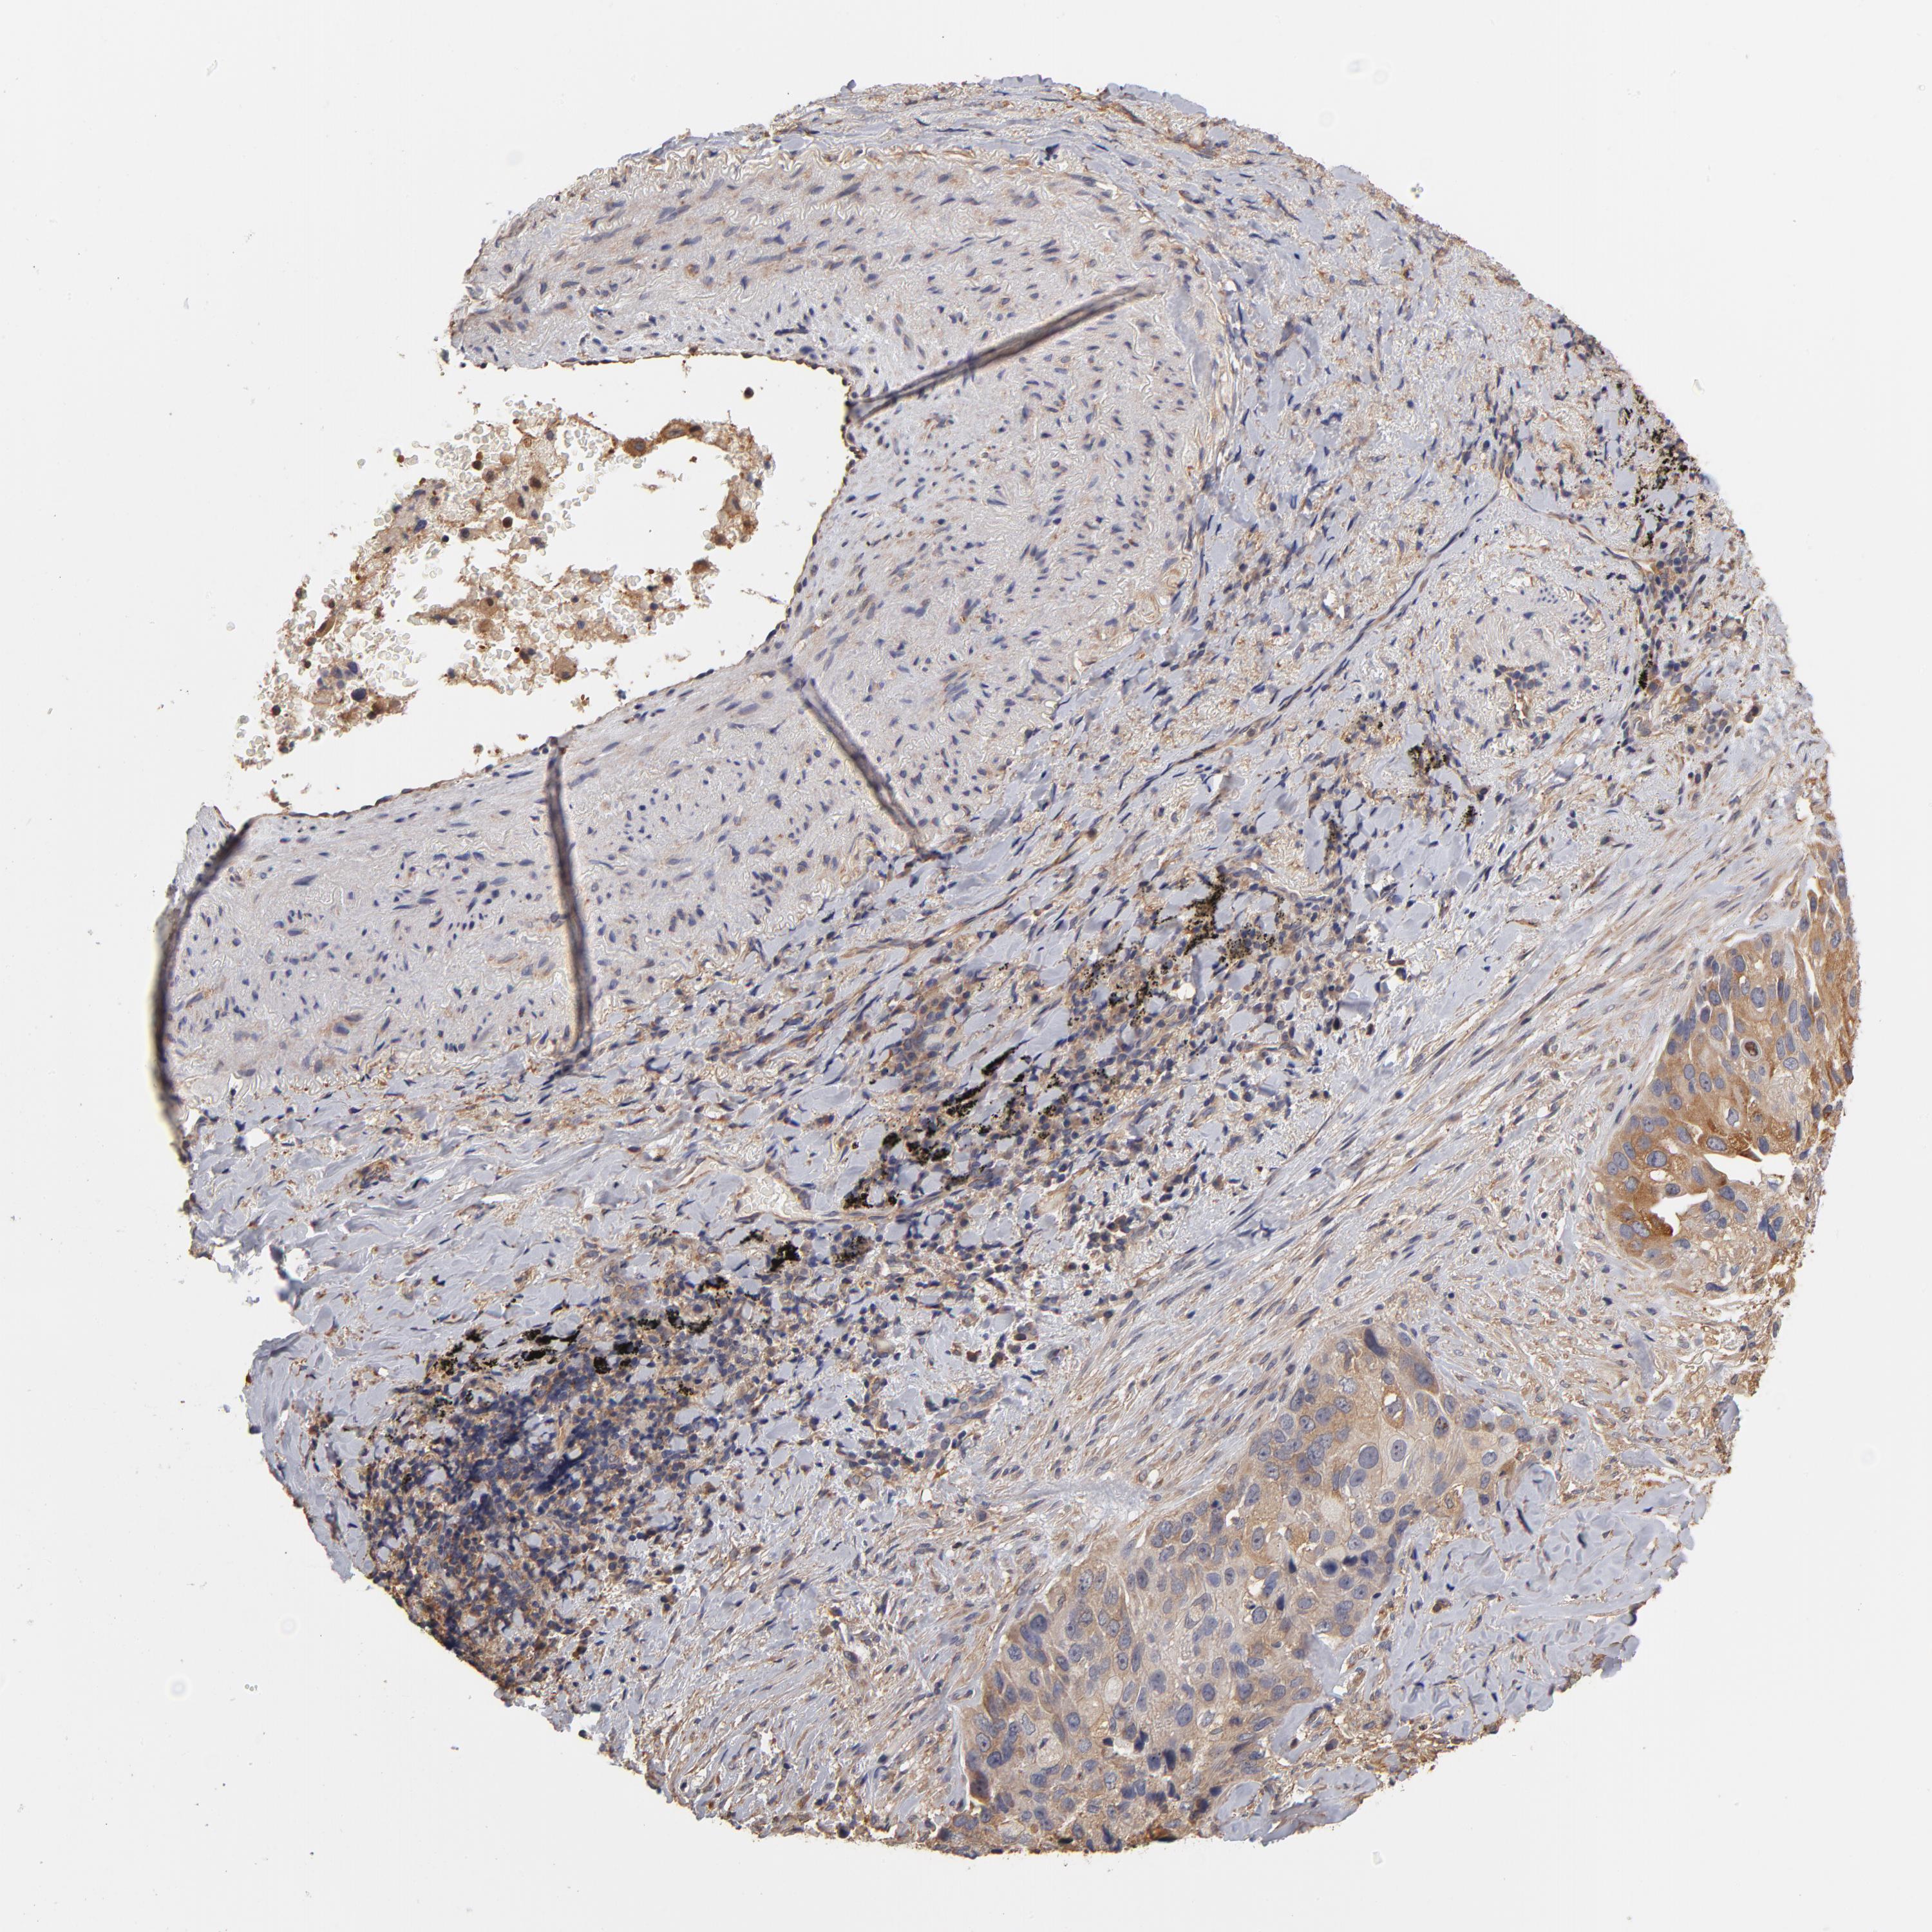

CANCER LUNG CANCER Show tissue menu

LUAD TCGA LUAD VALIDATION LUSC TCGA LUSC VALIDATION PROTEIN LUAD CPTAC PROTEIN LUSC CPTAC PROTEIN EXPRESSION